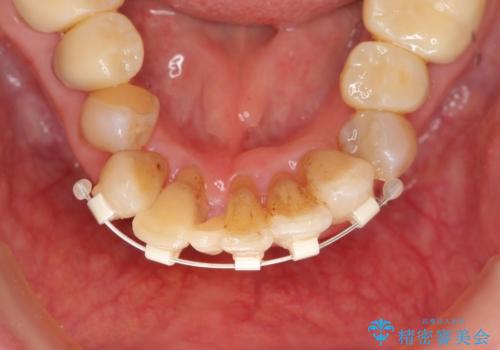

- 上顎前歯の黒ずみの改善、下顎前歯の十度なガタつき、矯正治療とセラミック治療を含む全体的な治療を希望され来院されました。

銀歯を高強度の仮歯に替えたのち、下顎前歯のみの部分矯正→全体的なマウスピース矯正治療(インビザライン)→最終的なセラミック治療と治療を進めます。